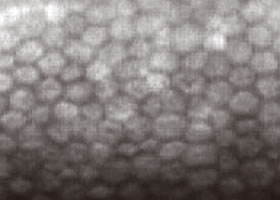

正常な角膜内内皮細胞

角膜内皮細胞の死滅減少→角膜の混濁[水疱性角膜症]→視力低下

継続的に酸素不足が続くと、角膜の細胞が死んでしまい、一度失った細胞は再生されることはありません。

また残っている細胞も大きさや形にばらつきが出てしまいます。